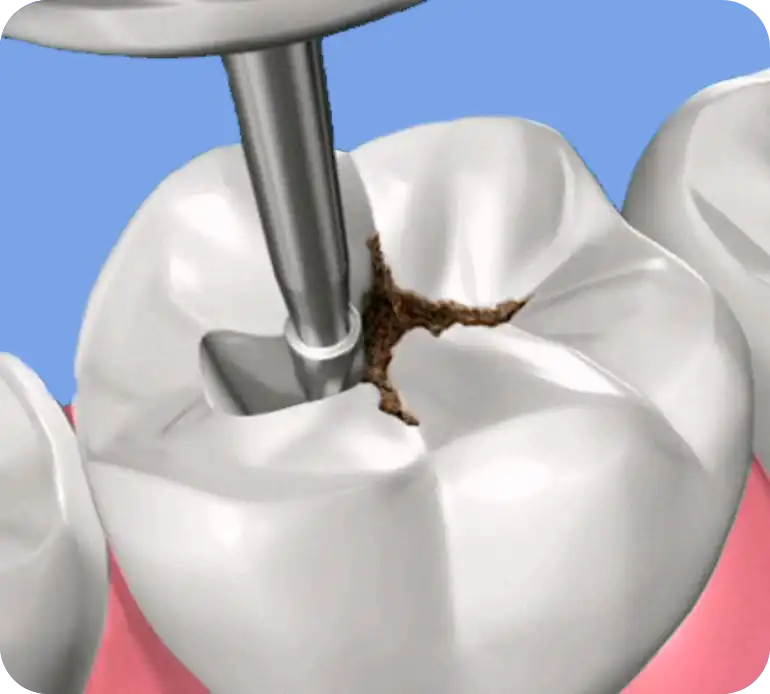

Hai i denti cariati?

Ti aiutiamo con la Conservativa

Utilizziamo tecniche all’avanguardia ed altamente estetiche, incluse la vetrificazione laser e l’uso di rilevatori di carie, per trattare i denti, preservandone la vitalità ed eliminare al 100% della carie.

Le nostre ricostruzioni in unica seduta sono progettate per ripristinare l’integrità e l’estetica dei tuoi denti, garantendo un sorriso non solo bello, ma anche sano